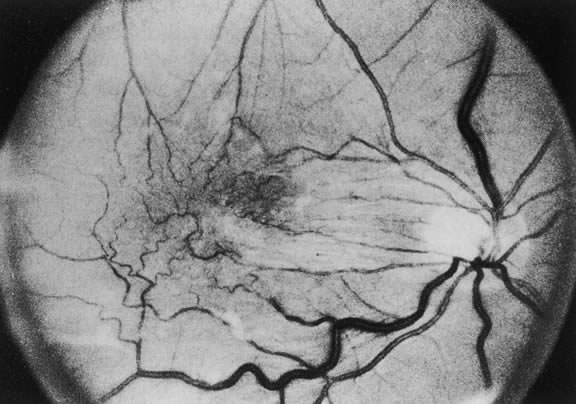

The nature of the adhesion between the vitreous cortex and the ILM is enigmatic. This adhesion is strongest at the optic nerve, the macula, the vitreous base, and retinal vessels. Foos6 demonstrated attachment plaques between Müller's cell cytoplasm and the ILM in the basal and equatorial retina (Fig. 2). Vitreous traction mediated by vitreous fibrils may contribute to these adhesions. These attachment plaques are not present posterior to the equator except where the ILM is thinned in the fovea. This anatomic variation in the fovea region may play a role in the pathogenesis of some of the vitreomacular disorders.

The ILM also thins over major blood vessels. Vitreous strands extend through pores in the ILM to surround the vessels11 and have been termed vitreoretinovascular bands.12 These bands may explain the strong adhesion between the vitreous and retinal vessels.

VITREOUS BASE

The vitreous base is a three-dimensional zone centered on the ora serrata where the vitreous is the most adherent to the retina and pars plana epithelium. It extends approximately 1.5 mm anteriorly to the ora serrata. Nasally, it extends 3.0 mm posterior to the ora and 1.8 mm posterior to the ora temporally. The functional base of the vitreous extends several millimeters into the vitreous body in this region. As the eye ages, the firm attachment of the vitreous base may extend posteriorly for several millimeters. This may lead to localized areas of enhanced vitreoretinal traction and result in retinal tears.

In the vitreous base, collagen fibers are relatively coarse, are numerous, and insert perpendicularly to the retina and pars plana. These fibers consist of collagen fibrils with diameters of 10.8 to 12.4 nm.16 The microscopic detail of the vitreous fibers attachment to the vitreous base varies from anterior to posterior. Anterior to the ora the fibers are less dense than posterior to the ora. Electron microscopic studies by Gartner17 demonstrate that the vitreous fibers have complex interdigitations with the reticular fibrillar materials of the basement membrane of the nonpigmented ciliary epithelium but do not pass between the cells. The anteriormost fibers splay out anteriorly to form the anterior loop of the vitreous base, which is important in the pathogenesis of anterior PVR.18 Posterior to the ora, bundles of vitreous fibrils attach to the ILM. Cords of vitreous collagen insert into gaps between the neuroglia. Gloor and Daicker19 likened this arrangement to Velcro and suggested that this may explain the strong vitreoretinal adhesion of the vitreous base. Cellular elements are also present in the vitreous base. Fibroblast-like cells are present anterior to the ora, and macrophage-like cells are posterior to the ora.17 These cells may play a role in the hypocellular gel contraction that characterizes anterior PVR.